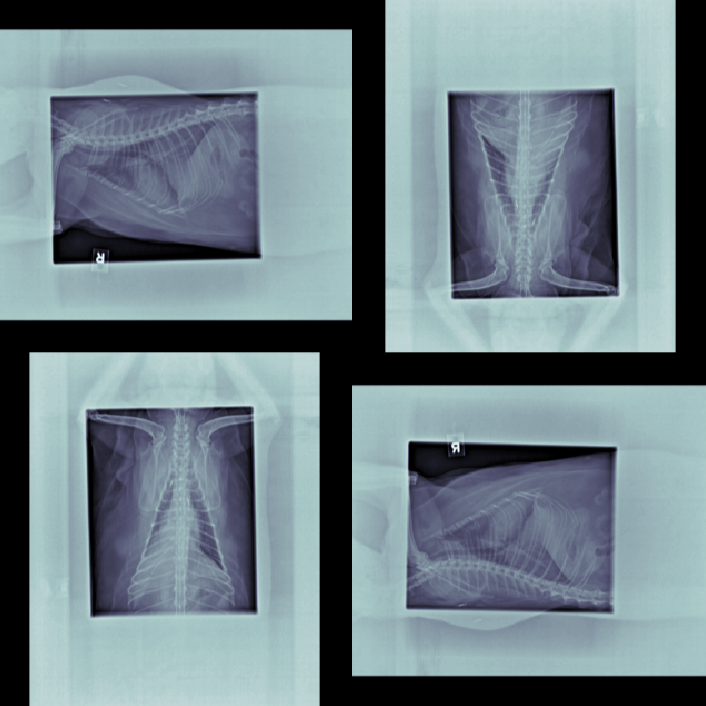

The data for this work consists of 390850 X-ray images, taken from 98660 veterinary sessions. These images were annotated by radiologists for over 41 diseases in a multi-label fashion, and are feedback from the usage of the RapidRead tool. Additionally, we have a dataset of 800 images with high-quality annotations, where the annotations were performed by 12 radiologists collaborating on each image. A sample of these X-ray images is shown in Figure 2.